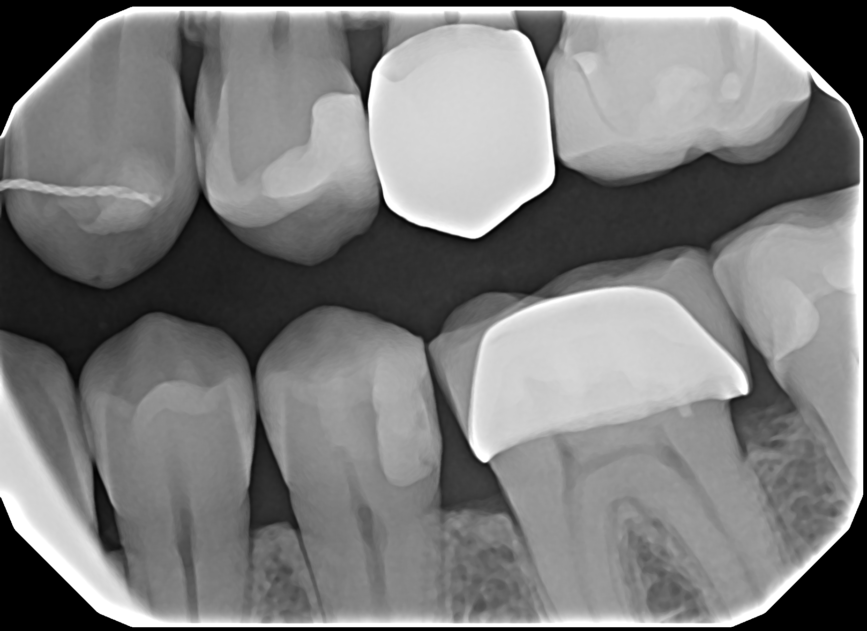

Crisp Images, Low Exposure

The low-noise design delivers exceptional clarity even at lower doses. Keeps patients safer while improving diagnostic confidence.

Capture Every Detail — High-Quality Imaging. Designed for Patient Comfort.

See The Clarity For Yourself

• Left Bitewing

• Mandibular Anterior

• Right Bitewing

• Maxillary Anterior